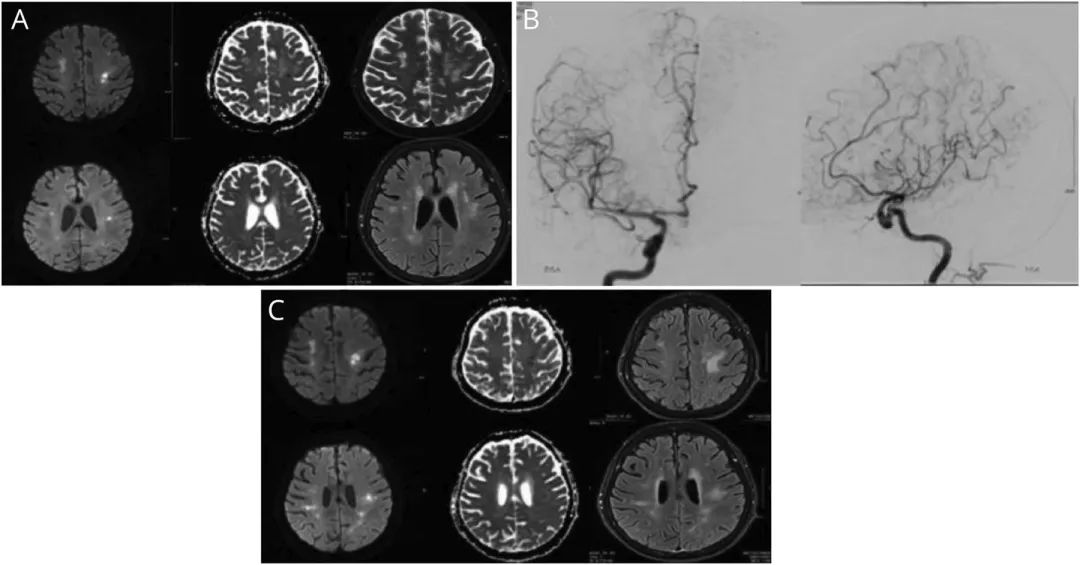

患者为84岁中国女性,因“亚急性认知功能下降3个月,发作性神经功能障碍2天”就诊。患者既往体健,2天内出现了多个单独的局灶性神经系统功能障碍发作(右侧无力伴失语,左侧无力) 。CT血管造影显示大脑中动脉多灶性狭窄和双侧M3段闭塞;后循环未见明显异常。头颅MRI显示双侧额叶和顶叶多发性局灶性弥散受限,弥漫性T2 /Flair信号改变而无异常增强,与梗死相符(图1,A)。患者开始使用小剂量乙酰水杨酸和深静脉血栓预防,并入院进一步诊治。

对于该患者,常规血管造影显示颅内外中小血管呈串珠样改变,提示弥漫性血管病变(图1,B)。血液检查显示炎症标记物升高(红细胞沉降速率115,C反应蛋白56.1),但风湿病学、凝血功能和感染性指标(包括抗磷脂抗体综合征和HIV)检测为阴性。CSF分析显示2个有核细胞,葡萄糖正常为2.3 mmol / L,蛋白质升高为1.46 g / L(正常范围:0.18–0.68),白蛋白升高为0.96 g / L(正常范围:0.14–0.25)。血清和脑脊液中均存在相同的寡克隆免疫球蛋白G条带,提示血脑屏障通透性增加。脑脊液细胞学检查为阴性。胸部、腹部和骨盆CT均未见实体器官恶性肿瘤或淋巴结肿大;副肿瘤抗体阴性。血清和尿液电泳未见明显异常。双侧颞动脉活检仅显示内弹性膜非特异性破坏,不能确定为巨细胞动脉炎(GCA)。

图1 患者头颅MRI检查结果。(A)最初的头颅MRI检查显示多灶性卒中。(B)常规血管造影图像显示颅内和颅外血管弥漫性串珠样改变。(C)复查头颅MRI显示新发缺血性卒中和陈旧缺血病灶的进展。

尽管进行了两*大轮**剂量的类固醇治疗,该患者仍反复卒中发作,复查MRI可见新发缺血性病变(图1,C)。